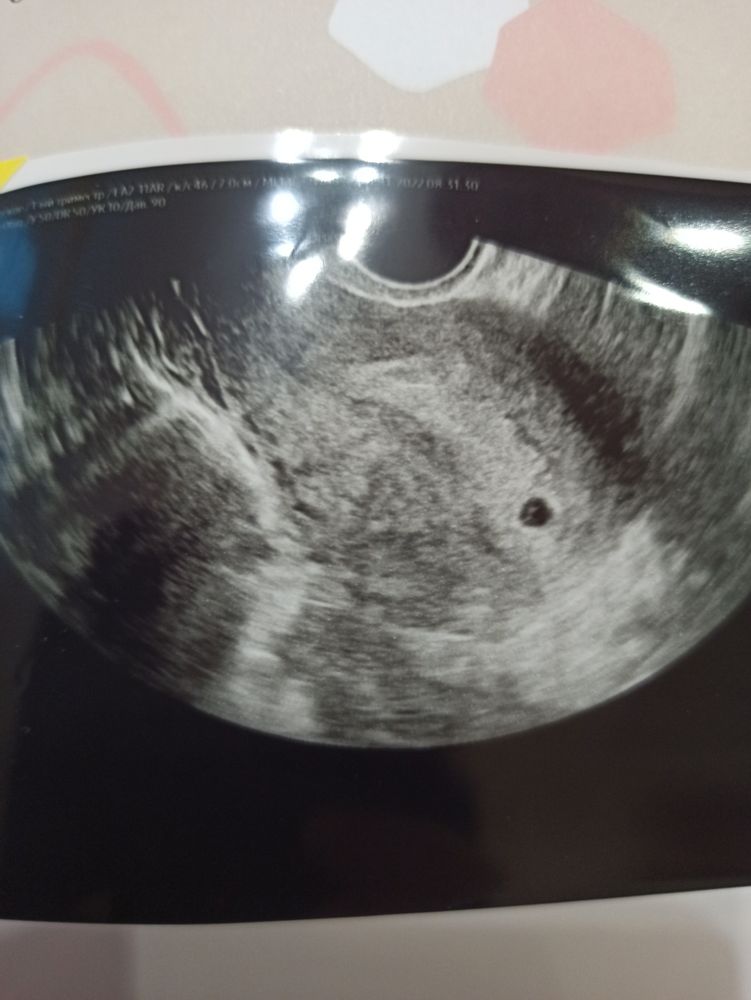

Саша, мужу долго думала как рассказать, искла интересные идеи, хотела сделать футболку сыну с надписью "старший брат" и в ней встретить с работы, но передумала, рассказала в 5 недель, когда убедилась сама, разбудила утром мужа с грустным лицом и фразой "я проглотила бусинку", он почти сразу всё понял, потом показала снимок УЗИ, на нем видно то как будто правда там бусинка, маме в 6 недель рассказала, чтоб не обижалась, что опять молчу, но всё равно она говорит что надо было сразу как узнала😁что долго молчу. Ей я загадала загадку: 4 глаза, 4 ноги, 4 руки, 2 сердца... это не монстр, кто это? Сыну на НГ расскажу, подарок сделаю, он очень ждёт малыша, будет рад, если ему рассказать рано, всем сам расскажет, не сможет сохранить в секрете, а вообще постараюсь больше никому из окружения не рассказывать, как можно дольше Изображение